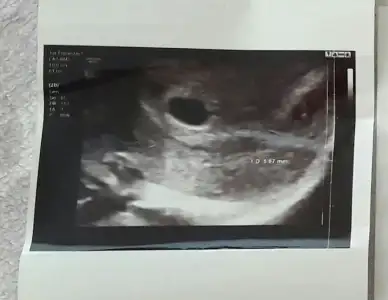

bu birinci gebeliğim

bu da 2.gebeliğim cinsiyet tahmini alabilir miyim ikisine de ikisi de 6 küsür haftalık usg ve karından